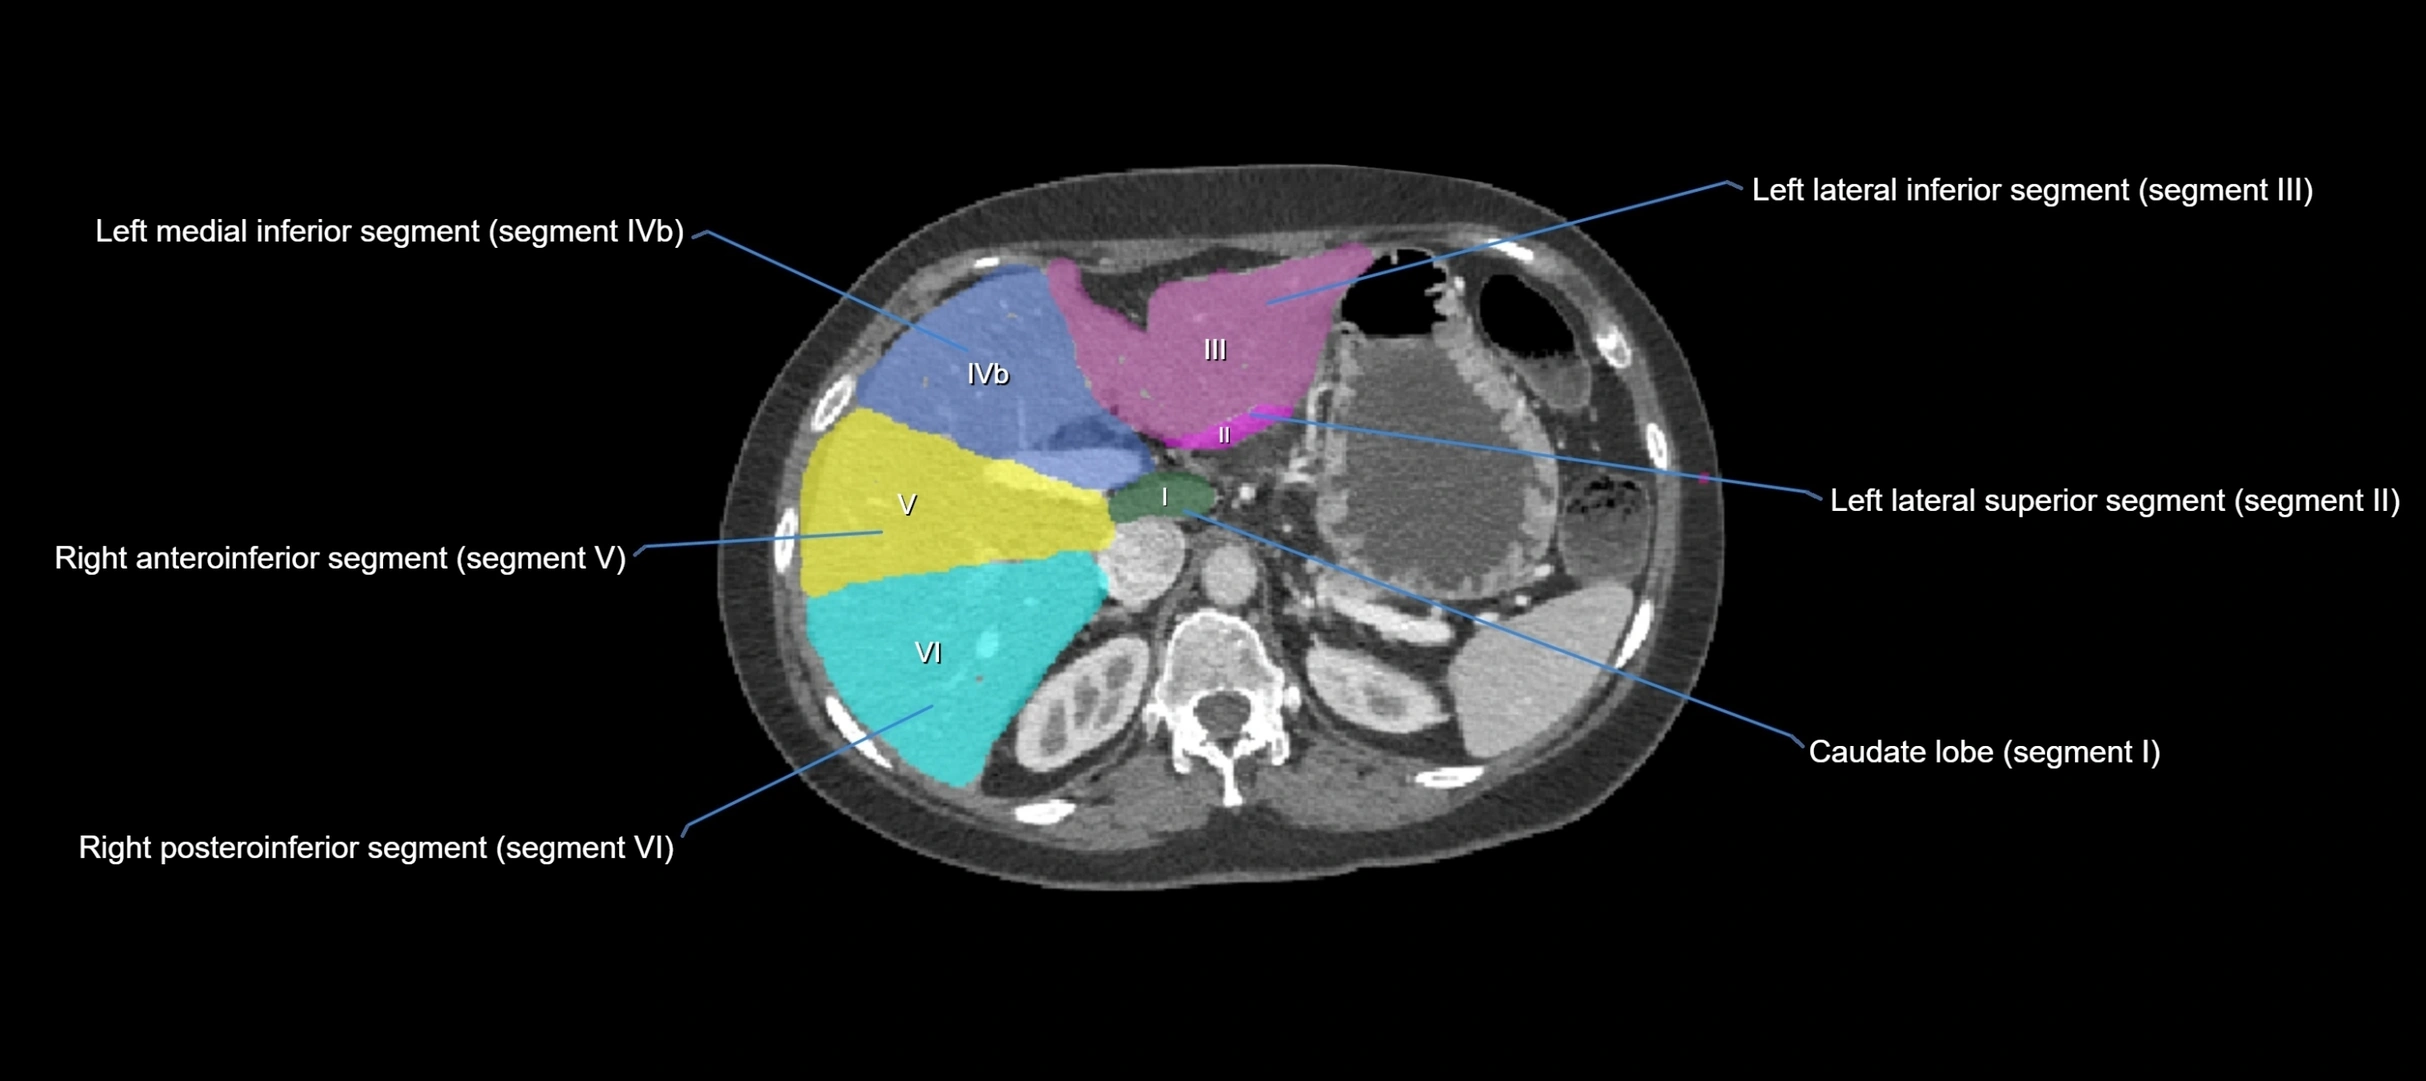

MRI image

image